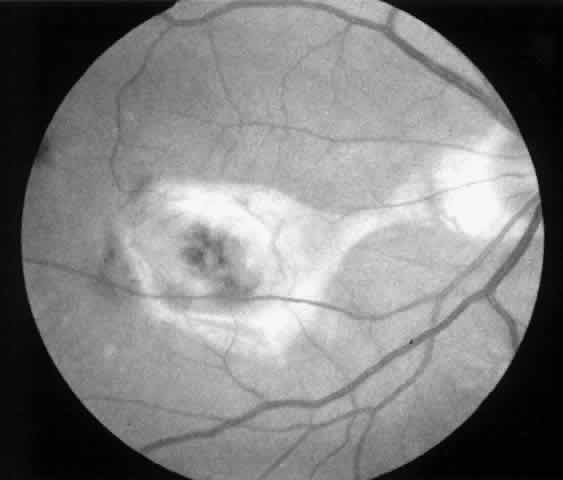

| Patients are examined 1 and 7 to 10 days after surgery to verify that intraocular pressure is acceptable, the retina remains attached, and no infection occurs. Three weeks after surgery, the view is usually adequate for assessment of the presence or absence of subfoveal RPE. Occasionally, residual subretinal blood will obscure the underlying tissues for a longer period of time. Within the first month, angiography is repeated to evaluate for recurrence of neovascularization. Not uncommonly, the site of the original choroidal ingrowth stalk demonstrates recurrent neovascularization. Often this site is not subfoveal and therefore slit lamp laser photocoagulation can be employed to ablate the recurrence. Given the fact that membranes recur in approximately one third of cases within 6 months, close follow-up is essential. |

MEMBRANES ANTERIOR TO RETINAL PIGMENT EPITHELIUM At the present time, we advise surgical extraction of a membrane only if the membrane appears to lie anterior to the RPE. In some cases, this is an easy determination to make preoperatively; in others, it is difficult. We study the macula with stereoscopic viewing at the slit lamp through a 60- or 78-diopter lens or with a contact lens. We also obtain color, stereo, 2× magnified views of the macula for subsequent review. The findings on clinical examination that suggest an anterior location may include the following:

Angiographic findings consistent with membranes anterior to the RPE include the following: